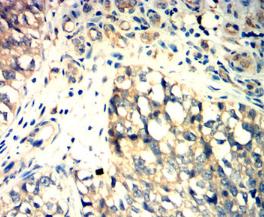

GPR56 Mouse Monoclonal antibody[3A1D7]

IHC    1/200 - 1/1000